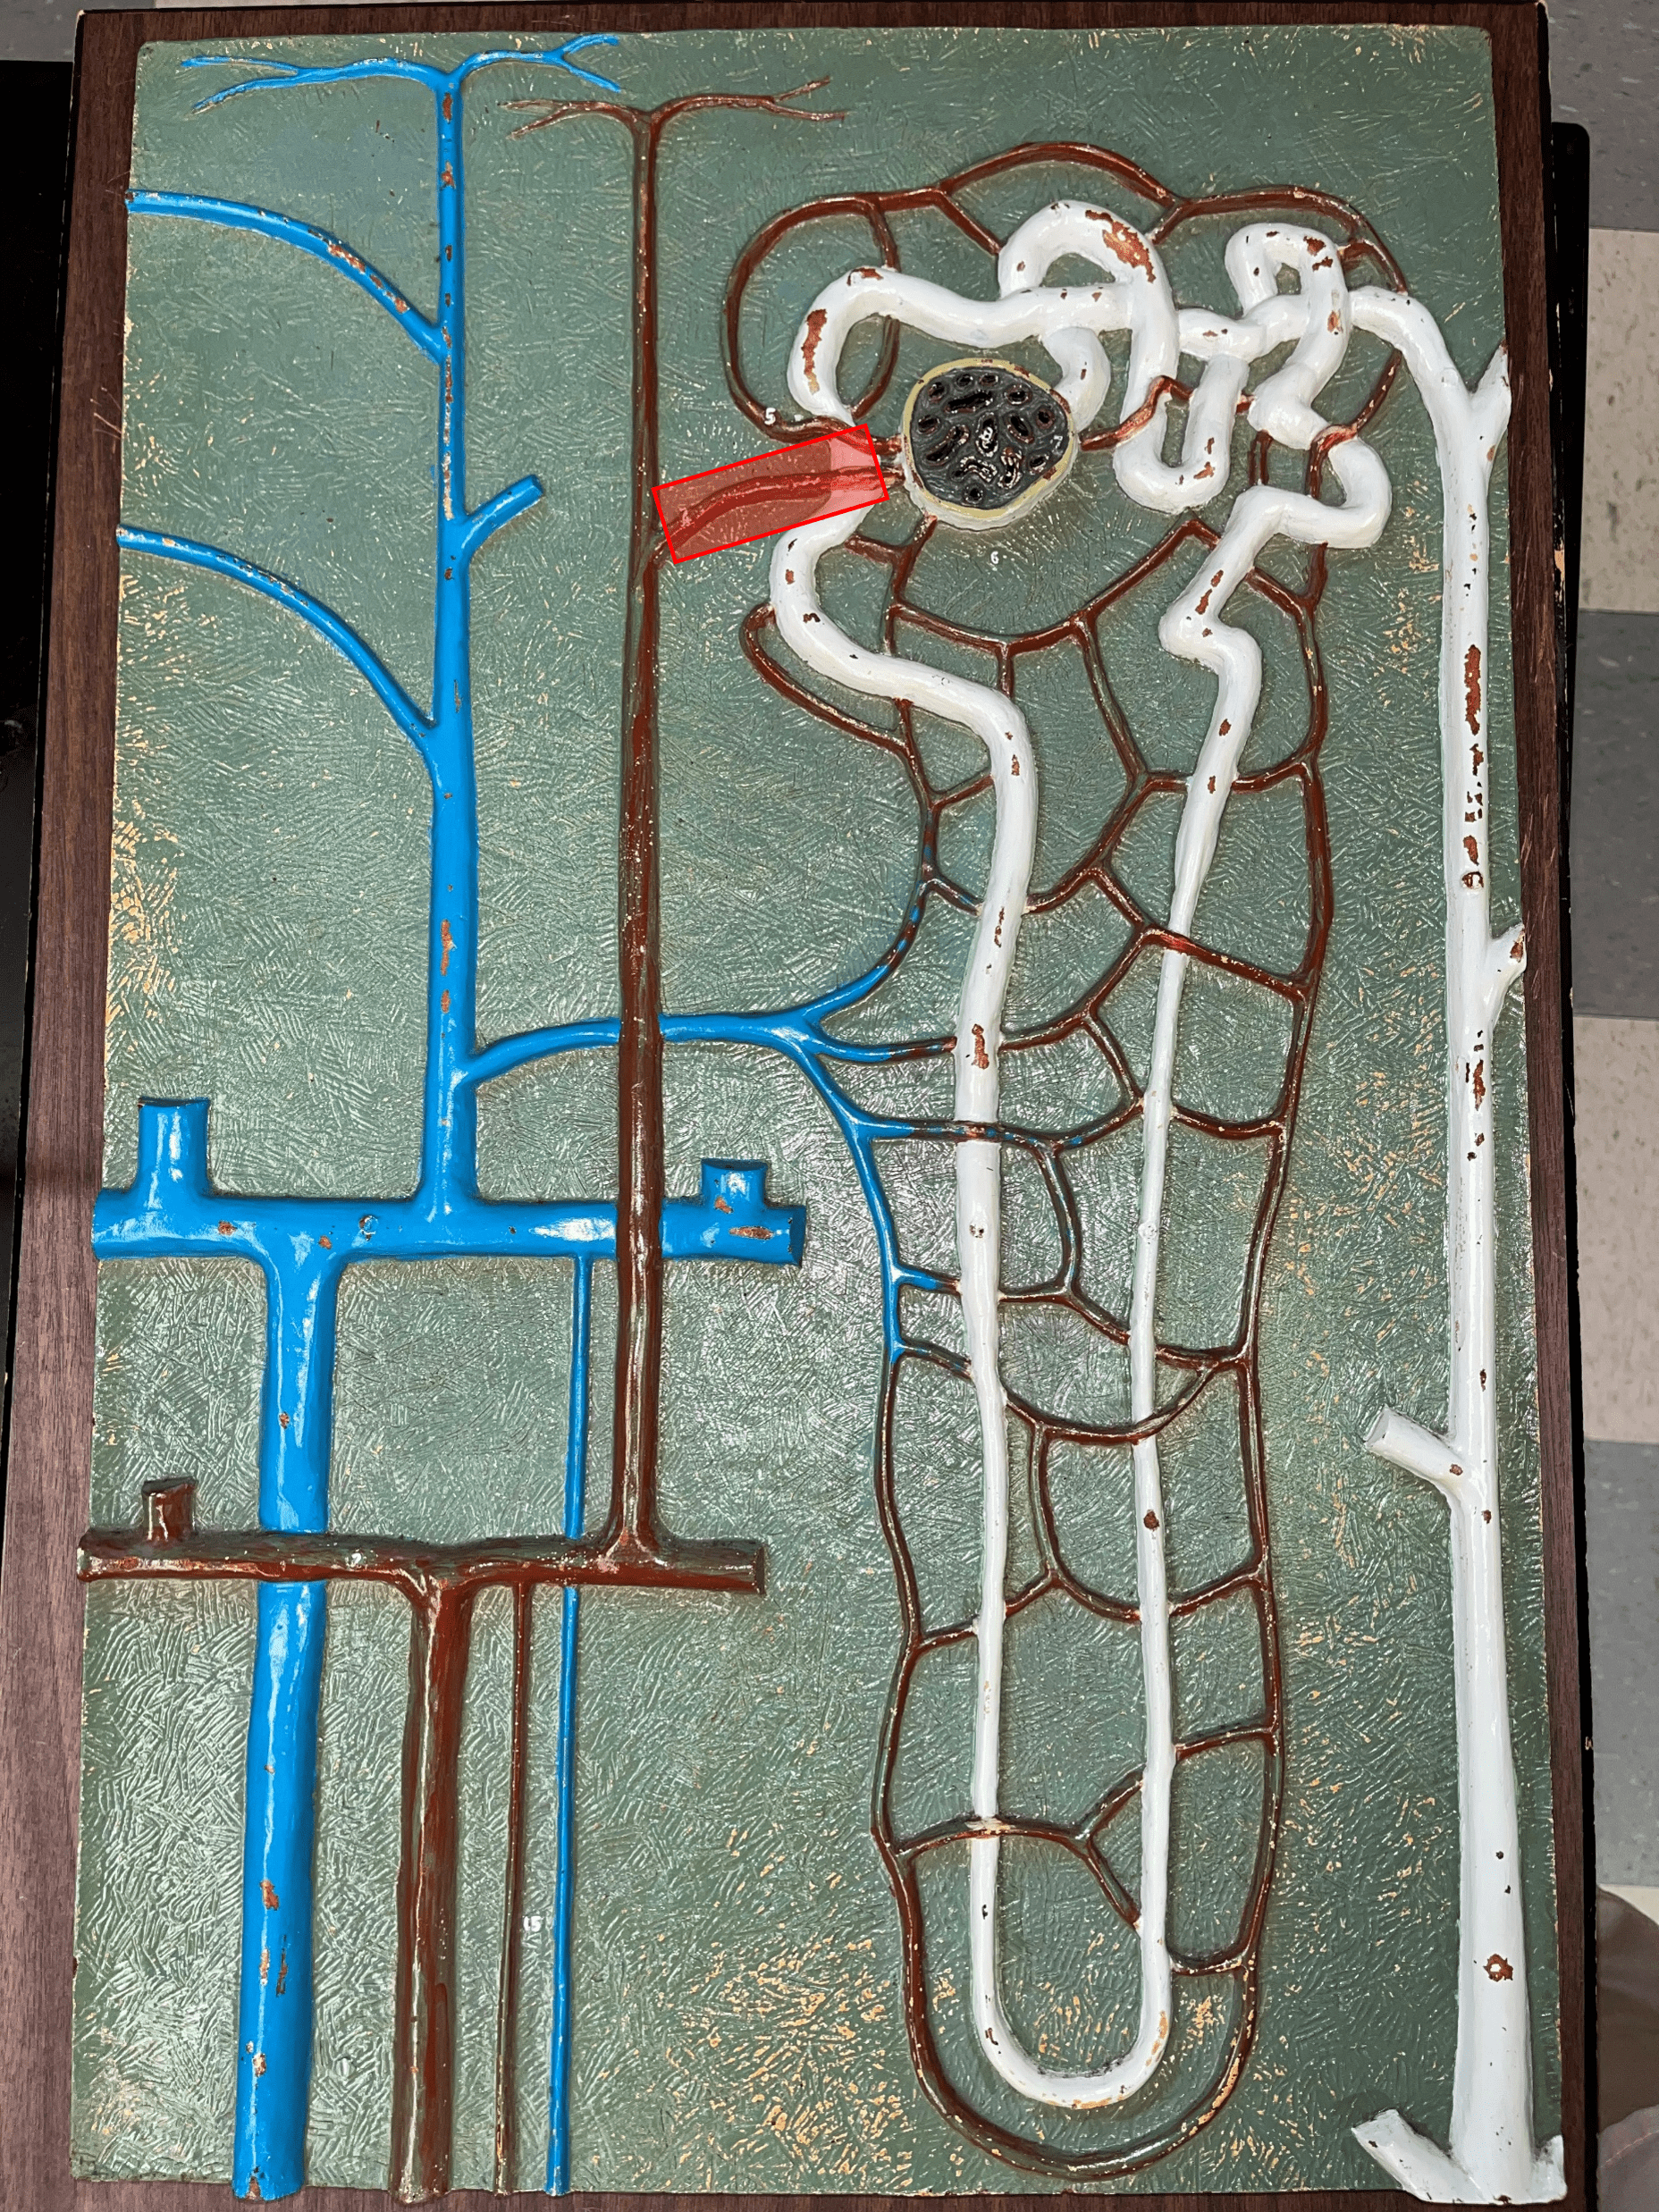

renal corpuscle

• Part of a nephron.

• Filters blood.

• Composed of a glomerulus enclosed within a glomerular capsule.

• Filters blood.

• Composed of a glomerulus enclosed within a glomerular capsule.

41

glomerulus

• Slide histology of the nephron.

• Part of a renal corpuscle.

• The capillary network of a renal corpuscle.

• Part of a renal corpuscle.

• The capillary network of a renal corpuscle.

42

capsular space

• Slide histology of the nephron.

• Part of a renal corpuscle.

• The interior of the glomerular capsule.

• Part of a renal corpuscle.

• The interior of the glomerular capsule.

43

glomerular capsule

• Slide histology of the nephron.

• Part of a renal corpuscle.

• A wall enclosing the glomerulus.

• Shown in the image is the parietal layer.

• Part of a renal corpuscle.

• A wall enclosing the glomerulus.

• Shown in the image is the parietal layer.

44

macula densa

• Part of a renal corpuscle.

• A group of columnar cells in the DCT that monitors fluid composition and filtration rate.

• A group of columnar cells in the DCT that monitors fluid composition and filtration rate.

47

afferent arteriole

• Branches of an interlobular artery.

• Supplies the glomerulus of a nephron for blood filtration.

• Supplies the glomerulus of a nephron for blood filtration.

efferent arteriole

Vessel carrying blood away from the glomerulus to the peritubular capillaries.